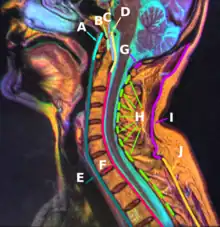

F: Posterior longitudinal ligament